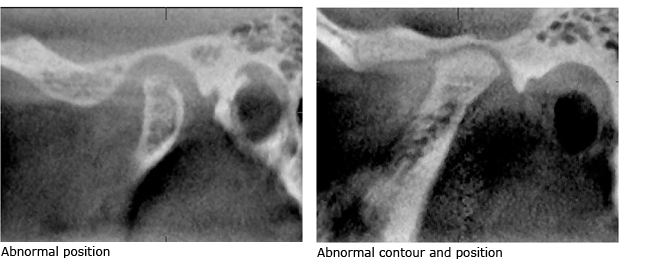

CBCT (sagittal view) of TMJ

MRI imaging of the articular disc within the TMJ

Image Comparison of MRI Normal/Abnormal Disc Position